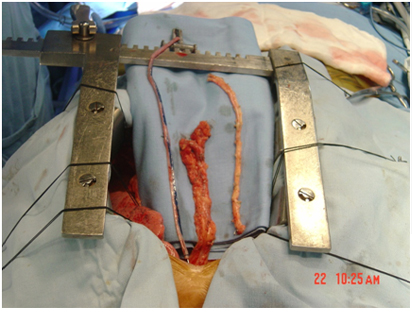

Conduits Used for Bypass grafting

Bypass Grafts